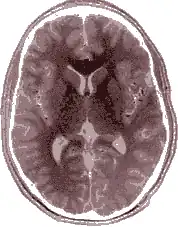

-

Einzelbild einer Magnetresonanz- tomographie eines menschlichen Gehirns; animierte Version mehrerer transversaler Schnittebenen

Einzelbild einer Magnetresonanz- tomographie eines menschlichen Gehirns; animierte Version mehrerer transversaler Schnittebenen -